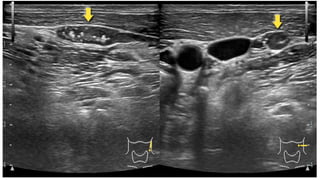

Pre-op TUMORS localization-

PRE-OP TUMOR LOALIZATION.

• Ultrasonography

• MRI

• CT

• Tl 201 – Tc99m scan

• 15.

Pre-op TUMORS localization- PRE-OPTUMOR LOALIZATION. • Ultrasonography • MRI • CT • Tl 201 – Tc99m scan